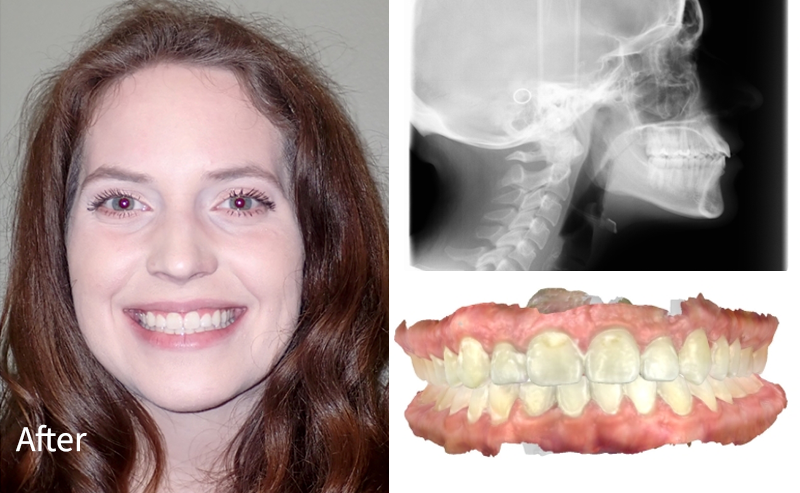

Crowding Corrected + Improved Bite

What we did

This patient had moderate crowding and bite imbalance. With braces, we aligned the teeth, created space where needed, and improved overall bite function for a healthier, more confident smile.